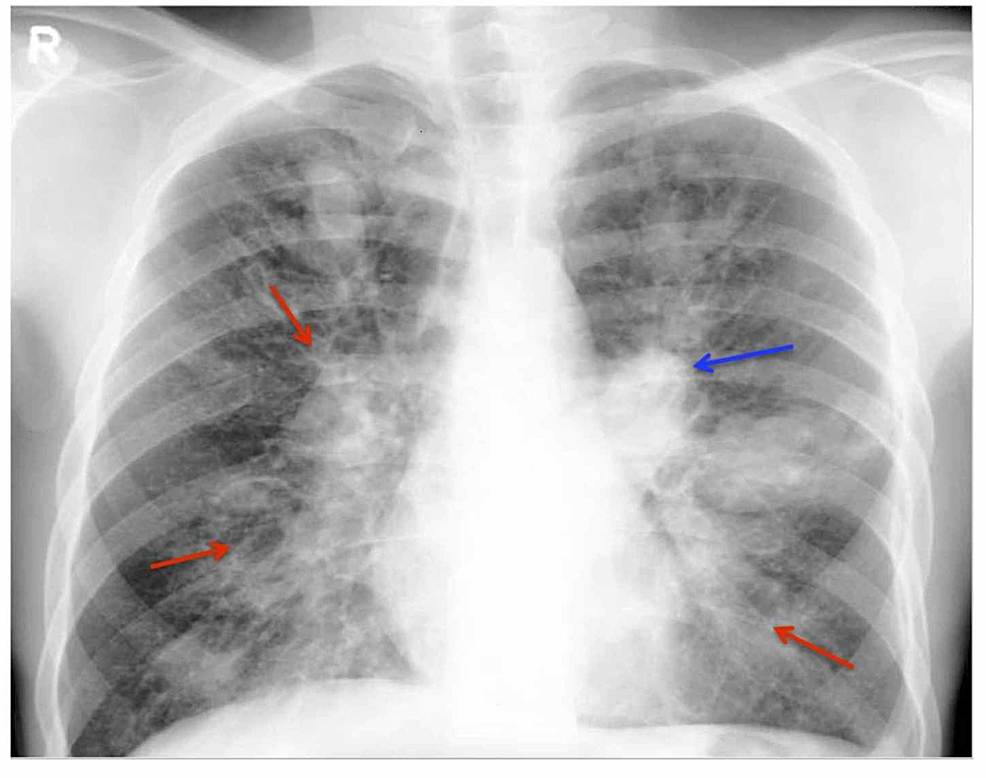

Рентгенологические изменения могут носить преходящий или постоянный характер. К преходящим признакам относятся:

- односторонние или двусторонние крупные уплотнения в лёгочной ткани;

- лёгочные инфильтраты;

- затемнения, которые образуются в результате закупорки повреждённого бронха слизью и напоминают по форме выдавленную из тюбика зубную пасту;

- тени дистальных бронхов, заполненных слизью — симптом «пальцев в перчатке»;

- симптом «трамвайных рельсов», свидетельствующий об утолщении стенок бронхов[9].

Рентгенография грудной клетки полезна для наблюдения, поскольку преходящие отклонения исчезают после начала терапии АБЛА[1].

Постоянные изменения — проксимальные бронхоэктазы, образующиеся на месте инфильтратов[7]. У больных бронхоэктазы выявляются в 80 % случаев[9].

Компьютерная томография грудной клетки является более чувствительным методом для выявления АБЛА. Наиболее частой находкой при КТ органов грудной клетки являются бронхоэктазы. Считается, что центральные бронхоэктазы более характерны для АБЛА, но почти в 40 % случаев они могут распространяться и на периферию лёгких. Также можно увидеть утолщение стенок бронхов, наличие слизистых пробок и изменения в окружающей лёгочной ткани[1].